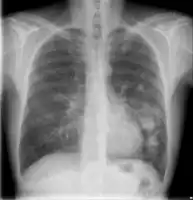

Chest X-ray of lungs affected by cryptococcosis -